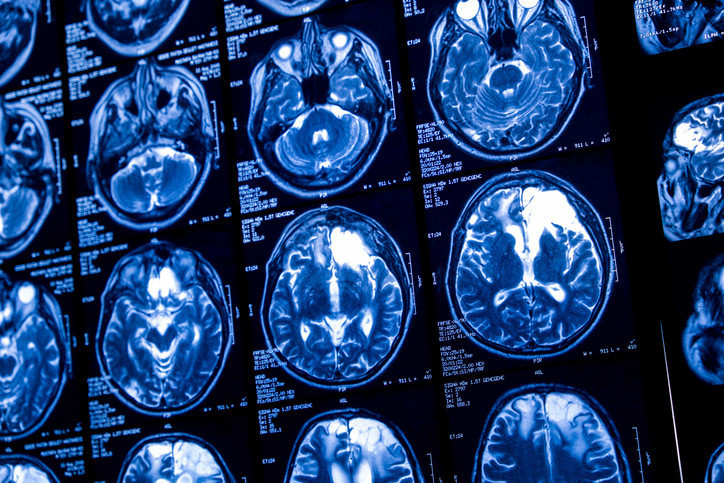

Yaklaşık bir yıl sonra hastada unutkanlık ve depresyon belirtileri ortaya çıktı. Bunun üzerine çekilen beyin MR’ında sağ frontal lobda bir lezyon fark edildi. Cerrahlar açık biyopsi sırasında hasarlı bölgeyi incelerken lezyonun içinde ip benzeri hareketli bir yapı gördü. Yapının yaklaşık 8 santimetre uzunluğunda canlı bir parazit olduğu anlaşıldı.